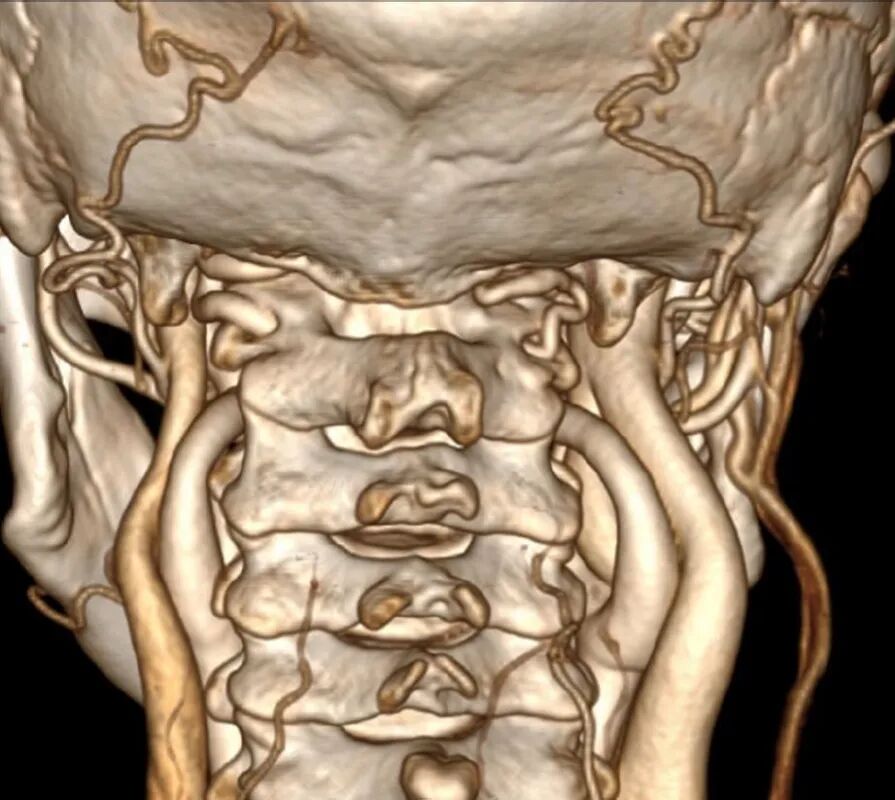

术前常规进行头颈部CTA扫描,应用计算机软件(推荐应用RadiAnt DICOM Viewer, Medixant Co.)对CTA Dicom数据进行三维重建详细观察颅颈交界区骨性结构畸形和椎动脉走行,制定手术方案,评估椎动脉损伤的风险。

根据进行关节间操作时损伤椎动脉的危险程度,将椎动脉走行分为3种类型:低风险型,高风险型,禁忌型低风险型椎动脉:椎动脉走行不遮挡寰枢椎关节面,进行关节间操作损伤椎动脉的风险较低,此类患者通常没有寰枕融合,或寰枕融合不完全,寰椎保留横突孔结构,椎动脉受到寰椎横突孔的引导,走行路径正常,没有遮挡寰枢椎关节面(图9)。